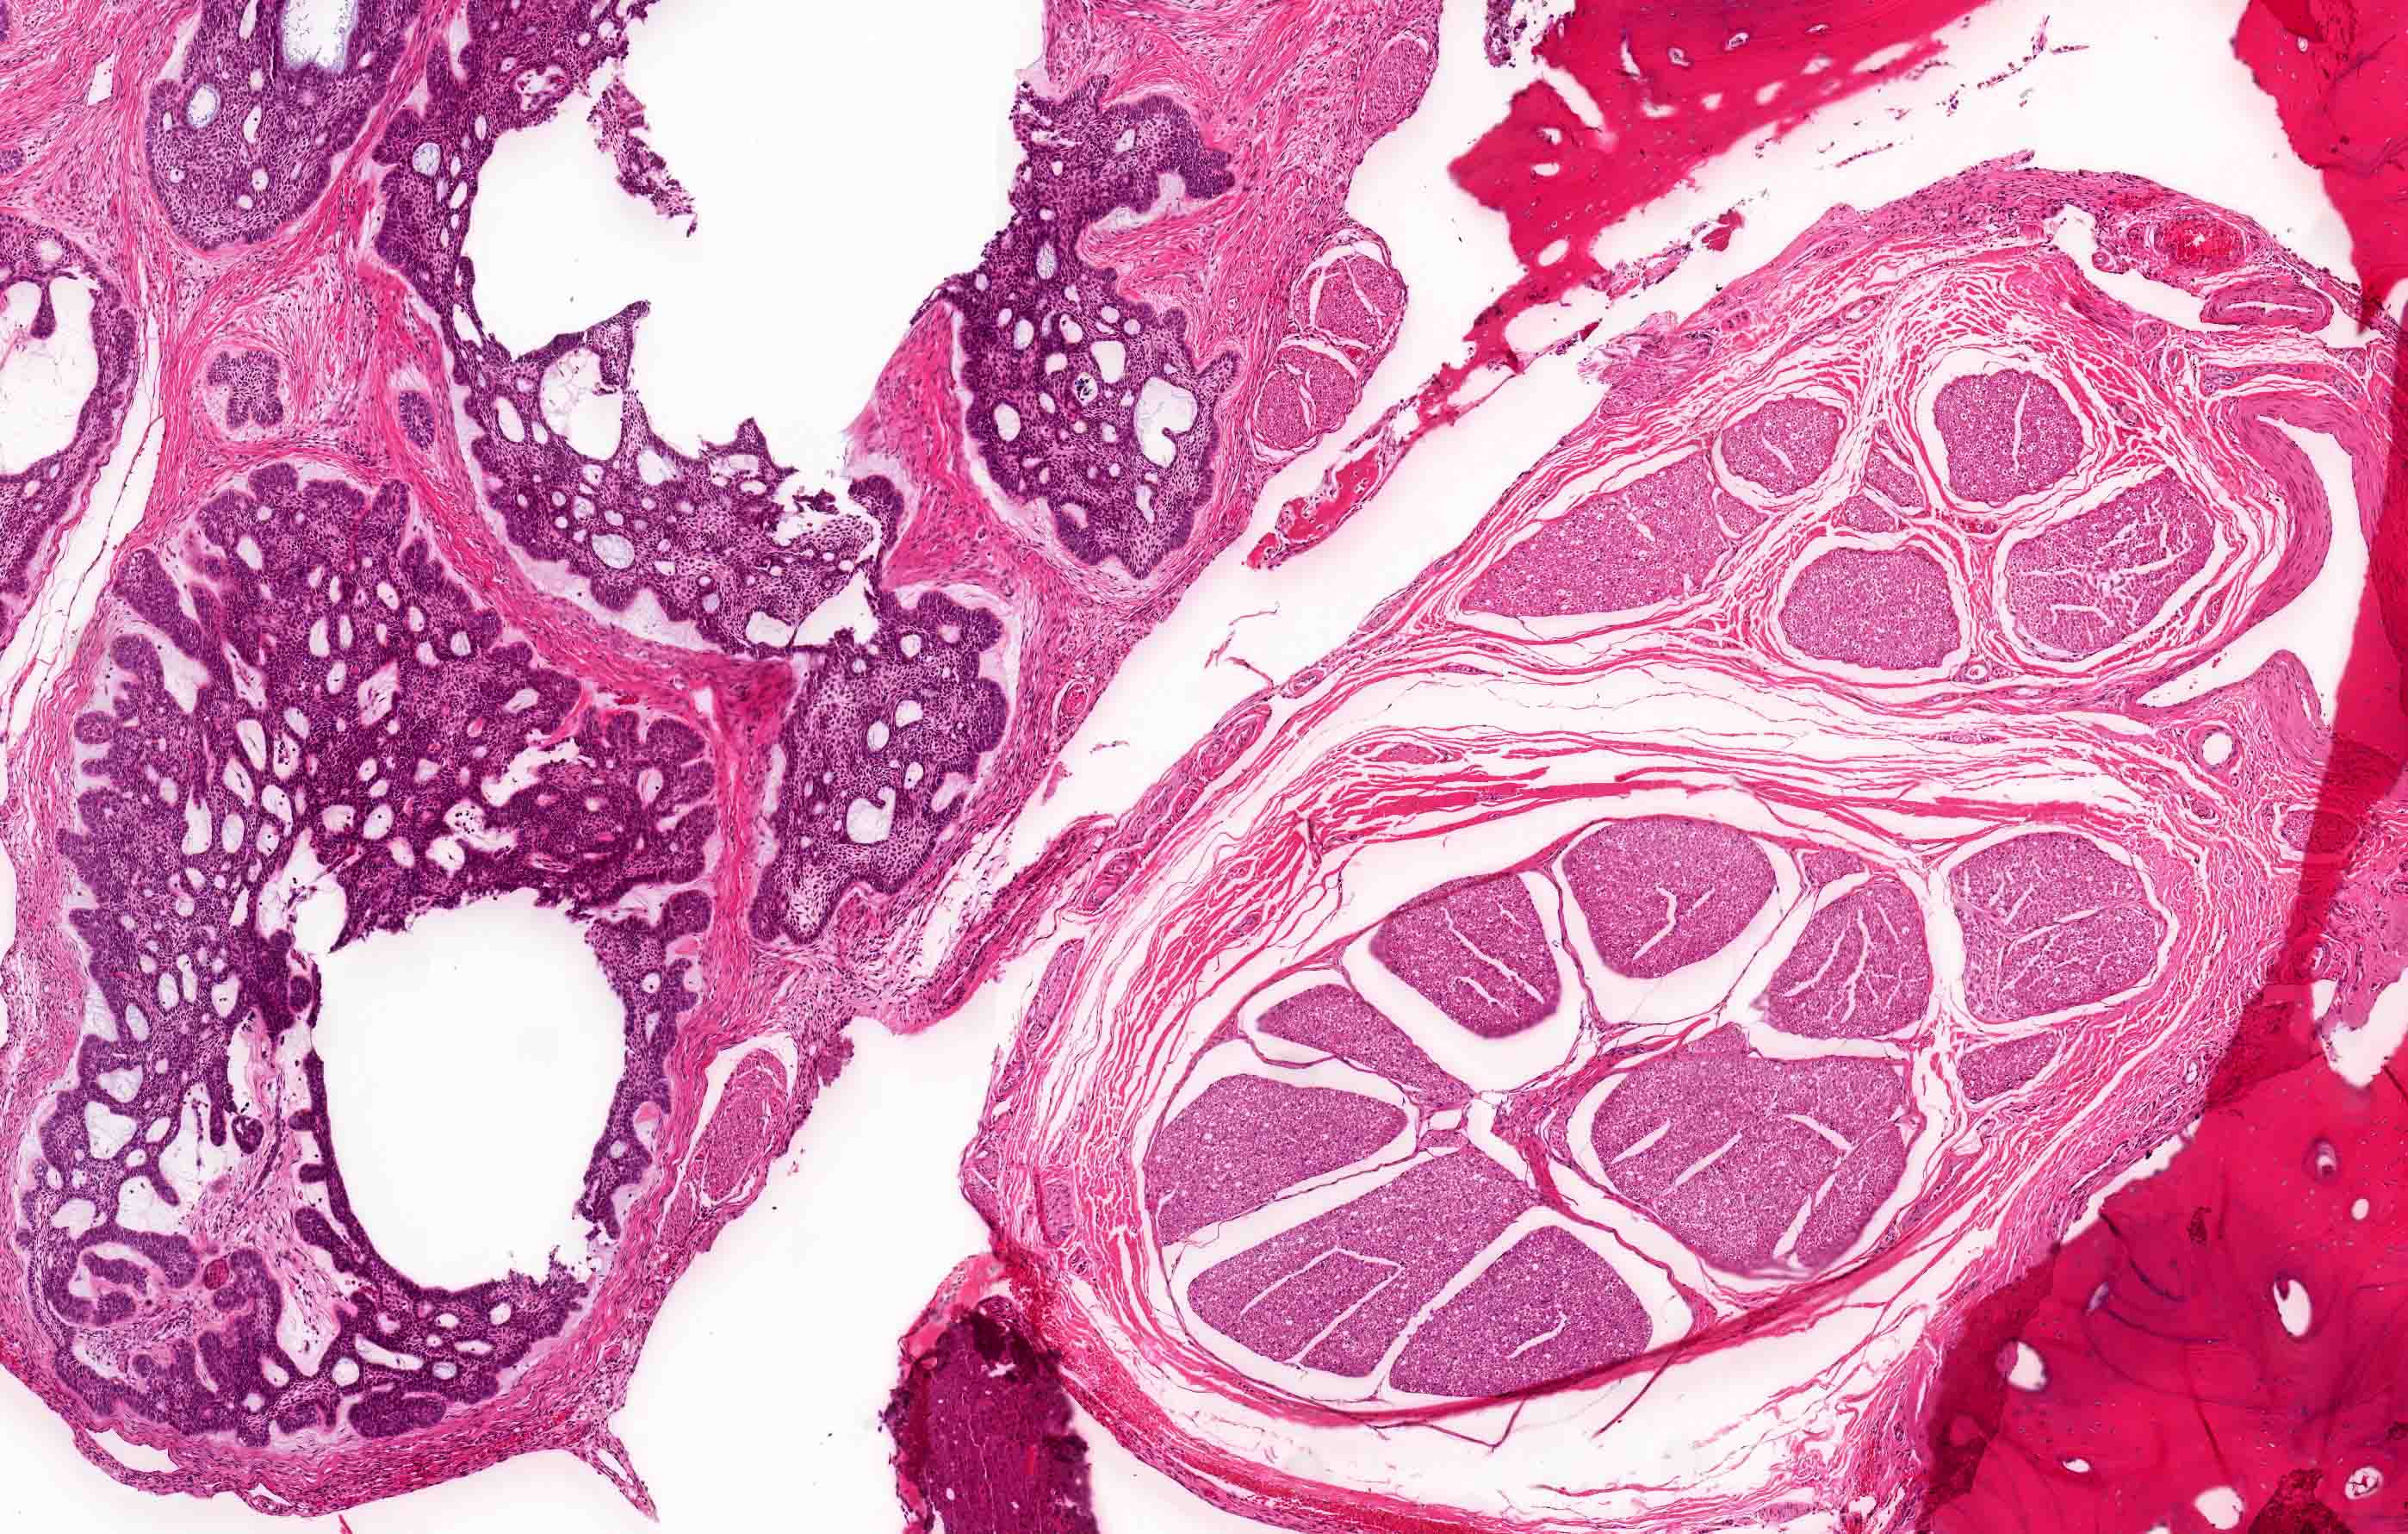

Microscopic (histologic) images

Contributed by Kelly Magliocca, D.D.S., M.P.H. and Anne C. McLean-Holden, D.M.D., M.S.

Microscopic (histologic) description

- Within the epithelial islands and cords of conventional ameloblastoma and the cystic epithelial lining of unicystic ameloblastoma, the odontogenic epithelium shows similar changes:

- Columnar cells with hyperchromatic nuclei at basal layer, exhibiting peripheral palisading

- Cells show reverse polarization away from basement membrane (Vickers-Gorlin change)

- Subnuclear vacuolization

- Suprabasal cells with a loose, network-like arrangement, recapitulating stellate reticulum formation seen in normal odontogenesis

- No dentin or enamel formation

- Follicular: most common subtype; islands of odontogenic epithelium in fibrous connective tissue; may be cystic; classic peripheral palisading and stellate reticulum-like areas

- Plexiform: cords and sheets of anastomosing odontogenic epithelial cells; classic peripheral palisading and reverse polarity not always obvious

- Ameloblastoma, unicystic type has 3 histopathological patterns

- Single cystic lesion lined by ameloblastic epithelium that shows typical features of ameloblastoma in some areas, including columnar basal cells in palisading arrangement with vacuolated cytoplasm, hyperchromatic nuclei polarized away from basement membrane

- Suprabasal cells loosely textured and noncohesive resembling stellate reticulum, epithelial invagination, epithelial edema and separation